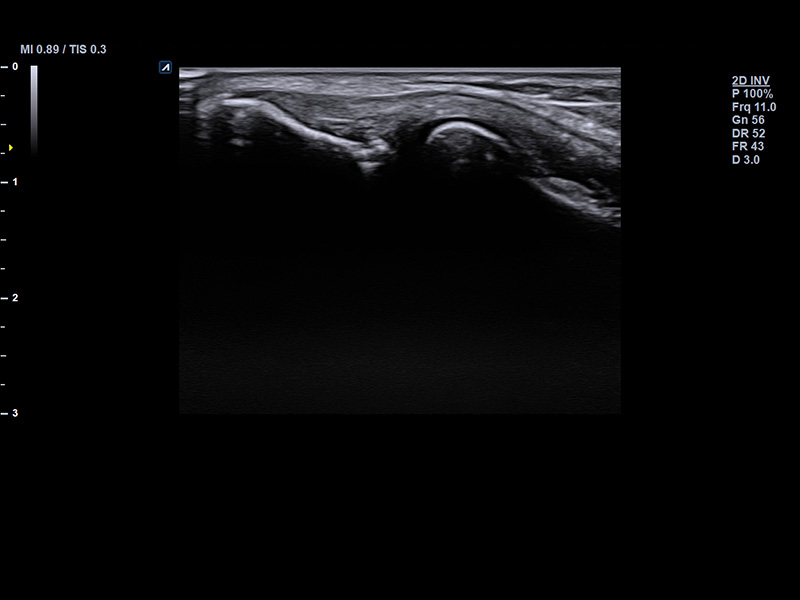

IO7-18

High frequency hockey stick (7-18MHz)

Application:

Small Parts, MSK